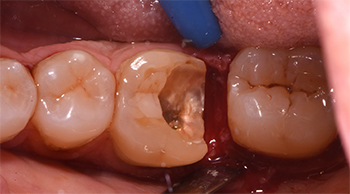

L’esecuzione di una radiografia endorale periapicale mostrava inoltre come tale frattura interessasse il tessuto d’attacco sovracrestale terminando 1 mm sottocresta.

Nell’ottica di una odontoiatria minimamente invasiva, si decideva dunque di eseguire un allungamento di corona clinica al fine di ristabilire una corretta connessione tra margine restaurativo ed ampiezza biologica e procedere dunque alla realizzazione di un overlay in disilicato di litio.